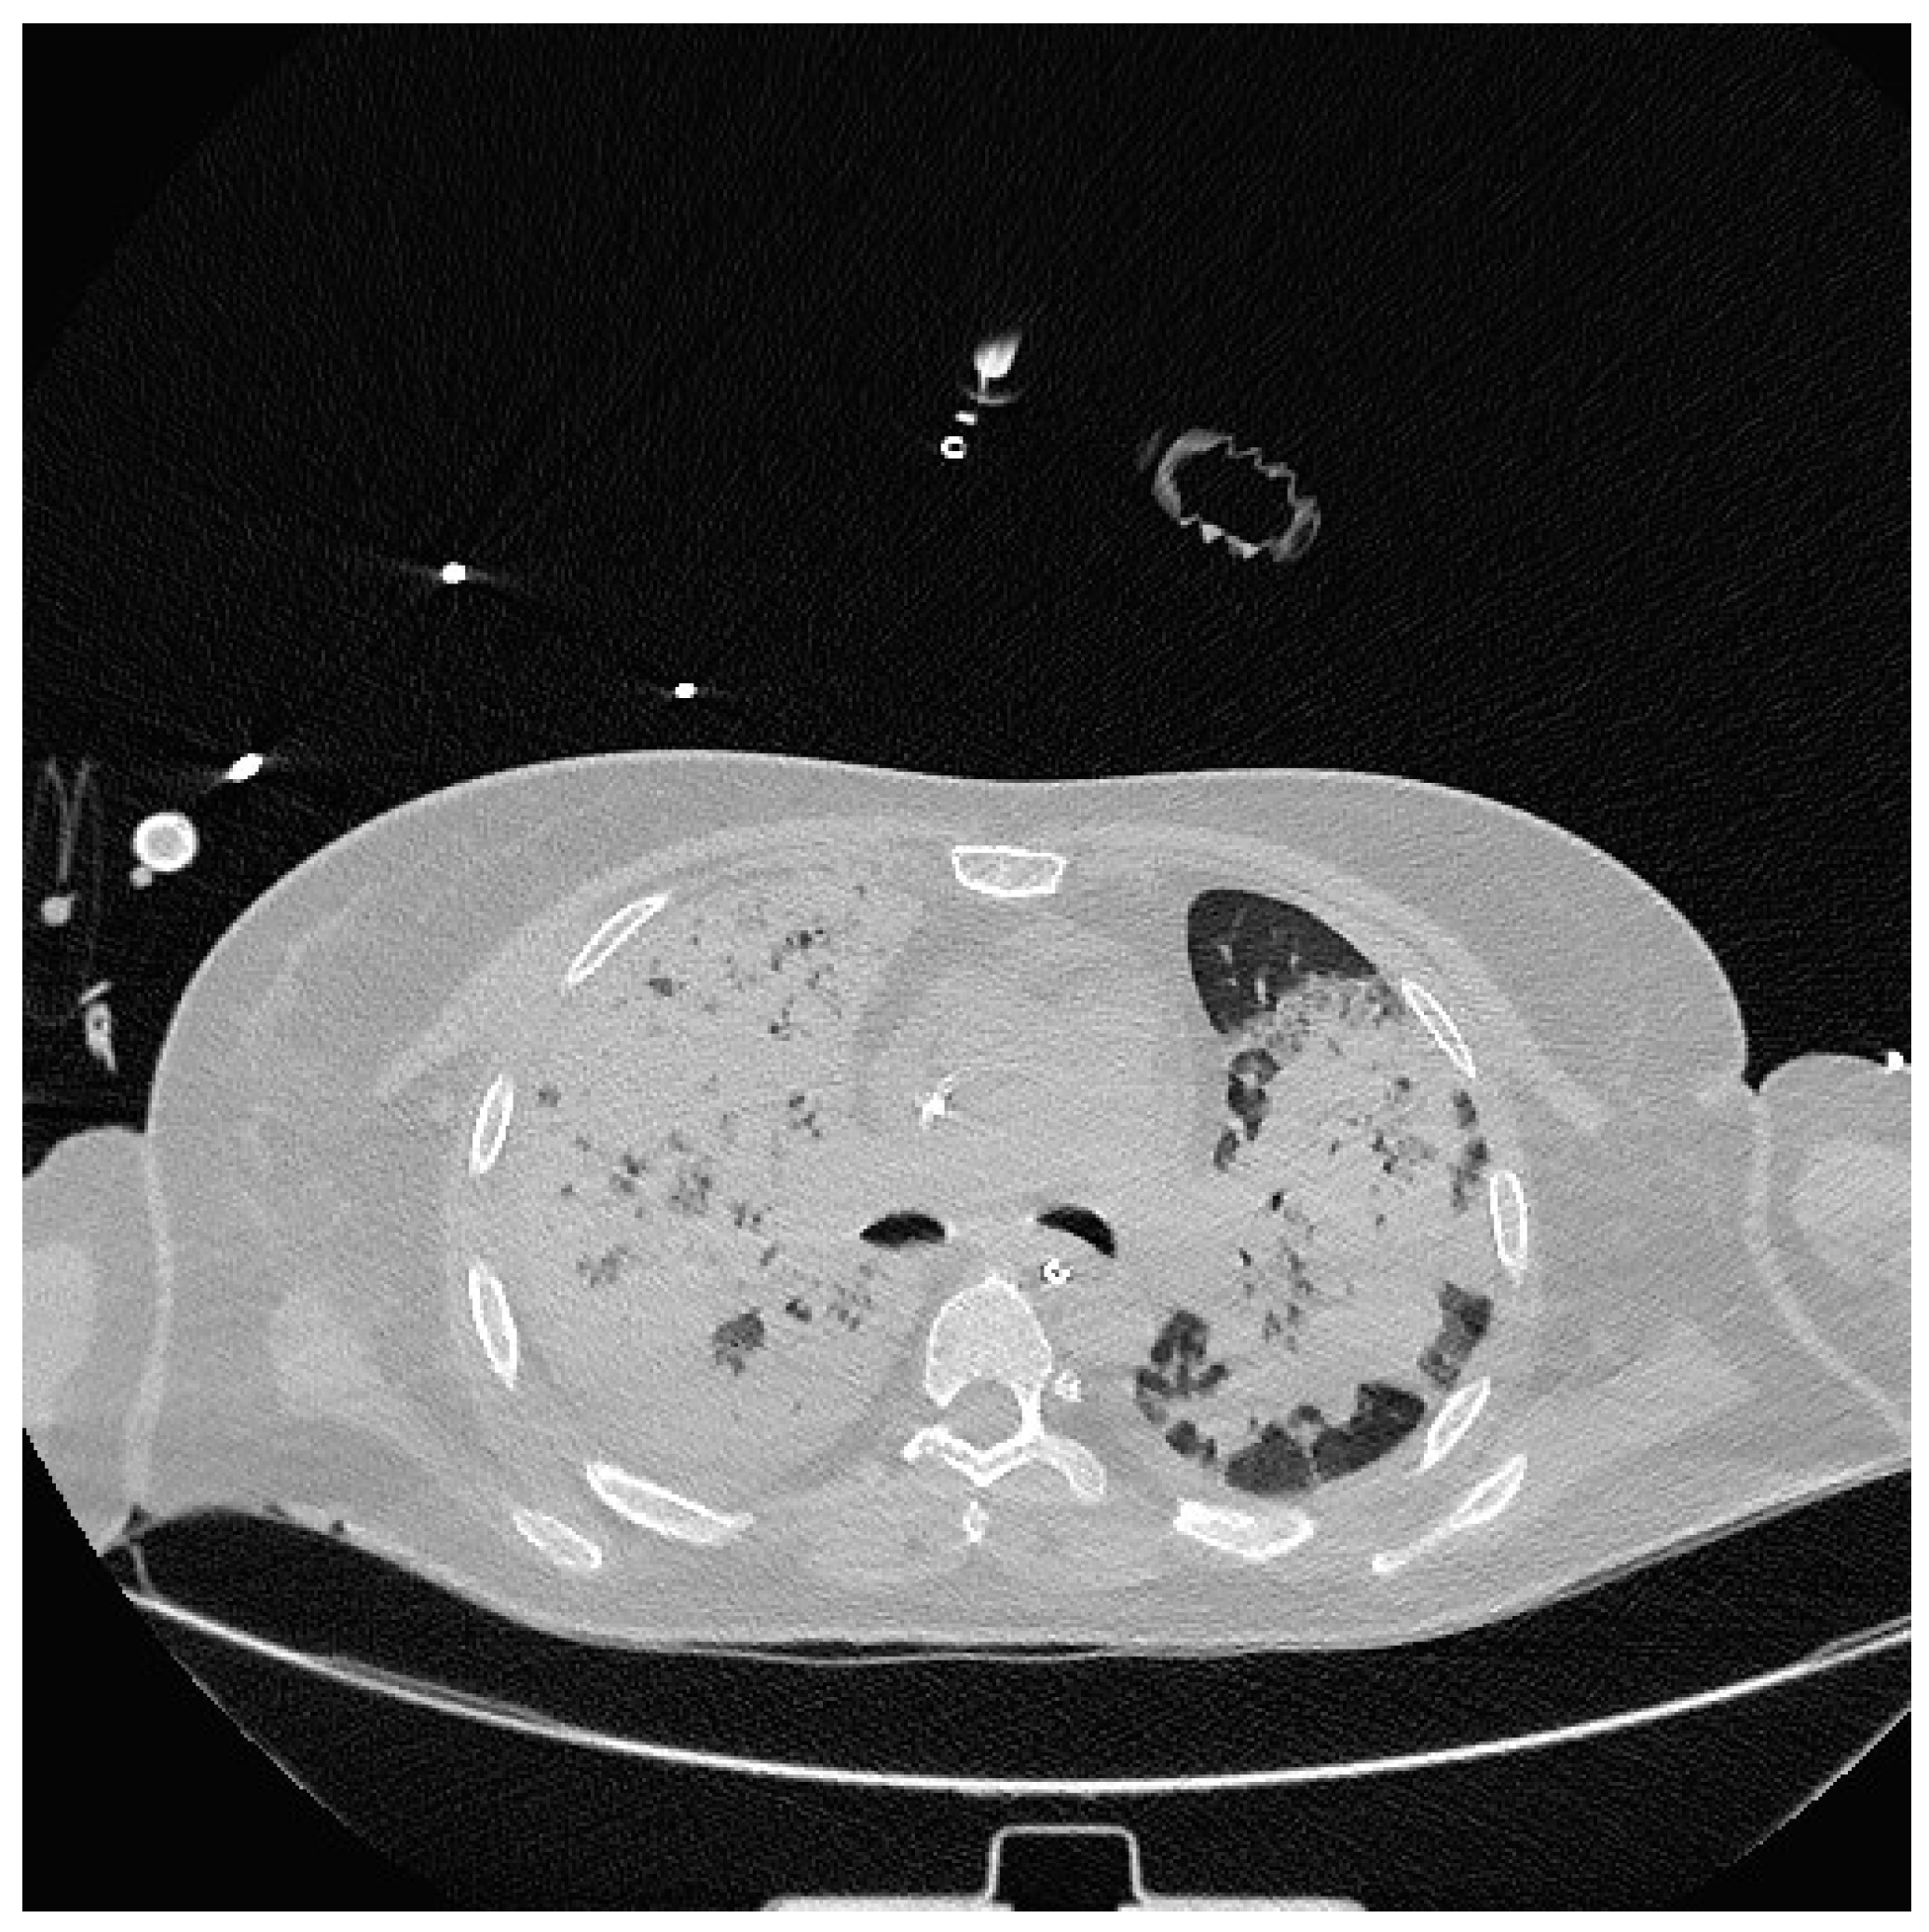

Severe hypoxia despite supplemental oxygen and respiratory distress required orotracheal intubation and mechanical ventilation in the emergency room. A chest CT scan was then performed which showed extensive consolidation of the right lung and subtotal consolidation of the left lung. (Figure 2).

Figure 2. CT Chest showing extensive parenchymal thickening of the entire right lung and subtotal of the left lung.